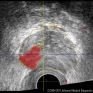

Jaunā aparatūra sniedz arī būtiskas priekšrocības pacientiem, kuriem nepieciešams izmeklēt prostatu. Izmantojot inovatīvo trīs dimensiju histoskenēšanas tehnoloģiju – Histoscanning™, urologi izmeklējuma laikā varēs novērtēt prostatas stāvokli, agrīni ieraugot prostatas izmainītos audus, kuri liecina par vēzi. Transrektālās ultraskaņas procedūras laikā tiek uzņemts augstas izšķirtspējas trīs dimensiju prostatas attēls, kurā no normāliem audiem atšķirīgie audi tiek iekrāsoti, tādējādi atvieglojot prostatas vēža diagnostiku. Turklāt aparatūra palielina biopsijas precizitāti, radot iespēju veikt tēmētu izmainīto audu paraugu paņemšanu un samazinot nelietderīgu biopsiju skaitu.

Procedūra, kas tiek veikta ar Histoscanning™, ieteicama kā daļa no prostatas izmeklēšanas kompleksa. Histoscanning™ nodrošina diferencētu prostatas audu attēlošanu. Tā raidītie signāli, kas vizualizē no prostatas normāliem audiem atšķirīgos audus, tiek iekrāsoti uz tradicionāli melnbaltā ultraskaņas attēla. HistoScanning™ aparatūrā izmantotā tehnoloģija tiek attīstīta un piemērota, lai nākotnē būtu iespējams veikt arī cita veida – krūts, olnīcu un vairogdziedzera vēžu diagnostiku.